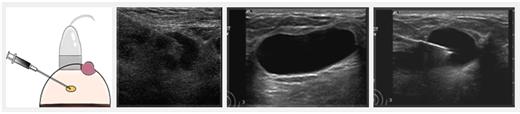

유방 조직검사(Breast Core Biopsy with Sonography)

유방 위치결정술(Breast Localization with Sonography)

유방 세침 흡인검사(Breast Aspiration with Sonography)